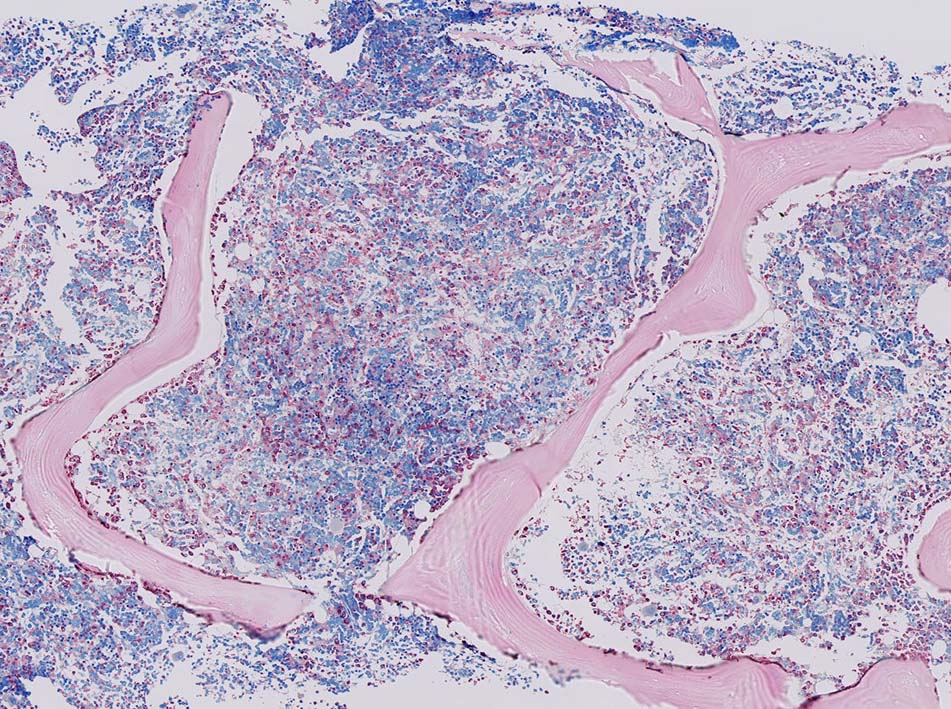

骨髄への腫瘍細胞浸潤はintertrabecular patternで, 腫瘍細胞は小集簇巣を形成して散在性に認められた. HE, ASD-Giemsaのみでの浸潤, 増殖の確定はなかなか難しいようです.

ASD-GiemsaではASDに染まらない(陰性の)あやしい細胞塊があるように見える. 細胞小塊はCD3陽性.

免疫染色でCD3陽性となる細胞集塊のASD-Giemsa像. 肝類洞内浸潤細胞に比較して核, 細胞が紡錘形の傾向を示している.